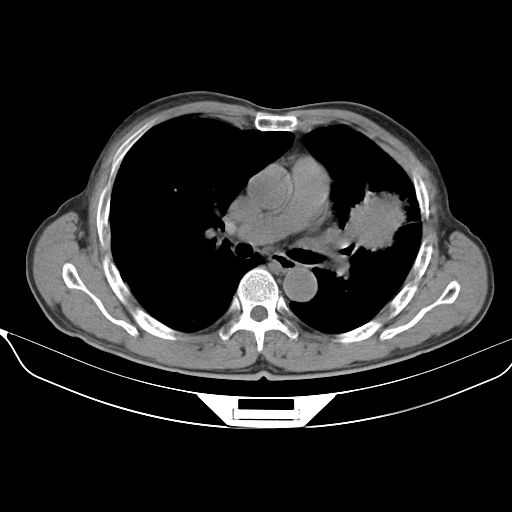

以下是引用心路寻觅在2010-3-1 10:23:00的发言:[br]1、考虑左肺上叶周围型肺癌[br]2、右上肺陈旧性病灶。[br][br][本贴已被 心路寻觅 于 2010-3-1 10:40:18 修改过]

以下是引用shuiyuan在2010-3-1 10:45:00的发言:[br]考虑左肺上叶中心型肺癌伴阻塞型炎症,邻近胸膜受侵。